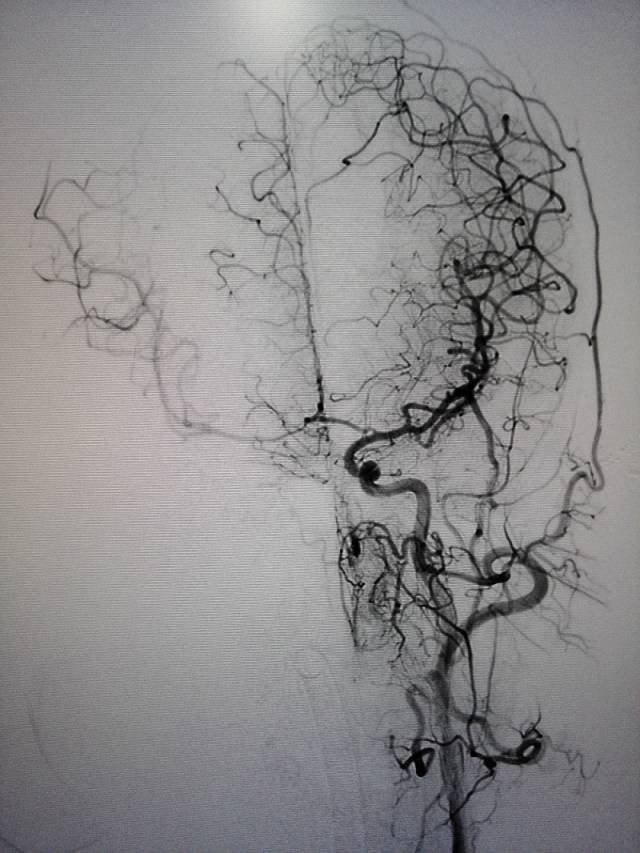

术前造影:右侧颈总动脉起始部显影,其余部位闭塞。颈外动脉向颈内动脉代偿供血。

经动脉鞘造影,可见颈总动脉通畅,但管腔狭窄,不规则。

然后球囊扩张,植入颈总动脉支架,造影示,右侧颈总动脉显影好。

此次分享两例颈动脉闭塞复合手术开通病例。第一例为颈内动脉长段闭塞,从颈内动脉起始段开始闭塞。患者术前存在眼动脉缺血事件及右侧半球灌注不足。颈内动脉剥脱后,颈内动脉可淡淡显影,为微导管通过创造条件。微导管通过后,顺利完成球囊扩张及支架植入,完全开通右侧颈内动脉。第二例为右侧颈总动脉闭塞患者,虽有颈外动脉代偿,但仍存在TIA及右侧大脑半球灌注不足。经颈动脉内膜剥脱后,造影可见颈总动脉显影,但管腔严重不规则,经球囊扩张及支架植入后,颈总动脉显影好。两例患者术后7天复查颈动脉CTA,均显示颈内动脉起始处较术后造影增粗。